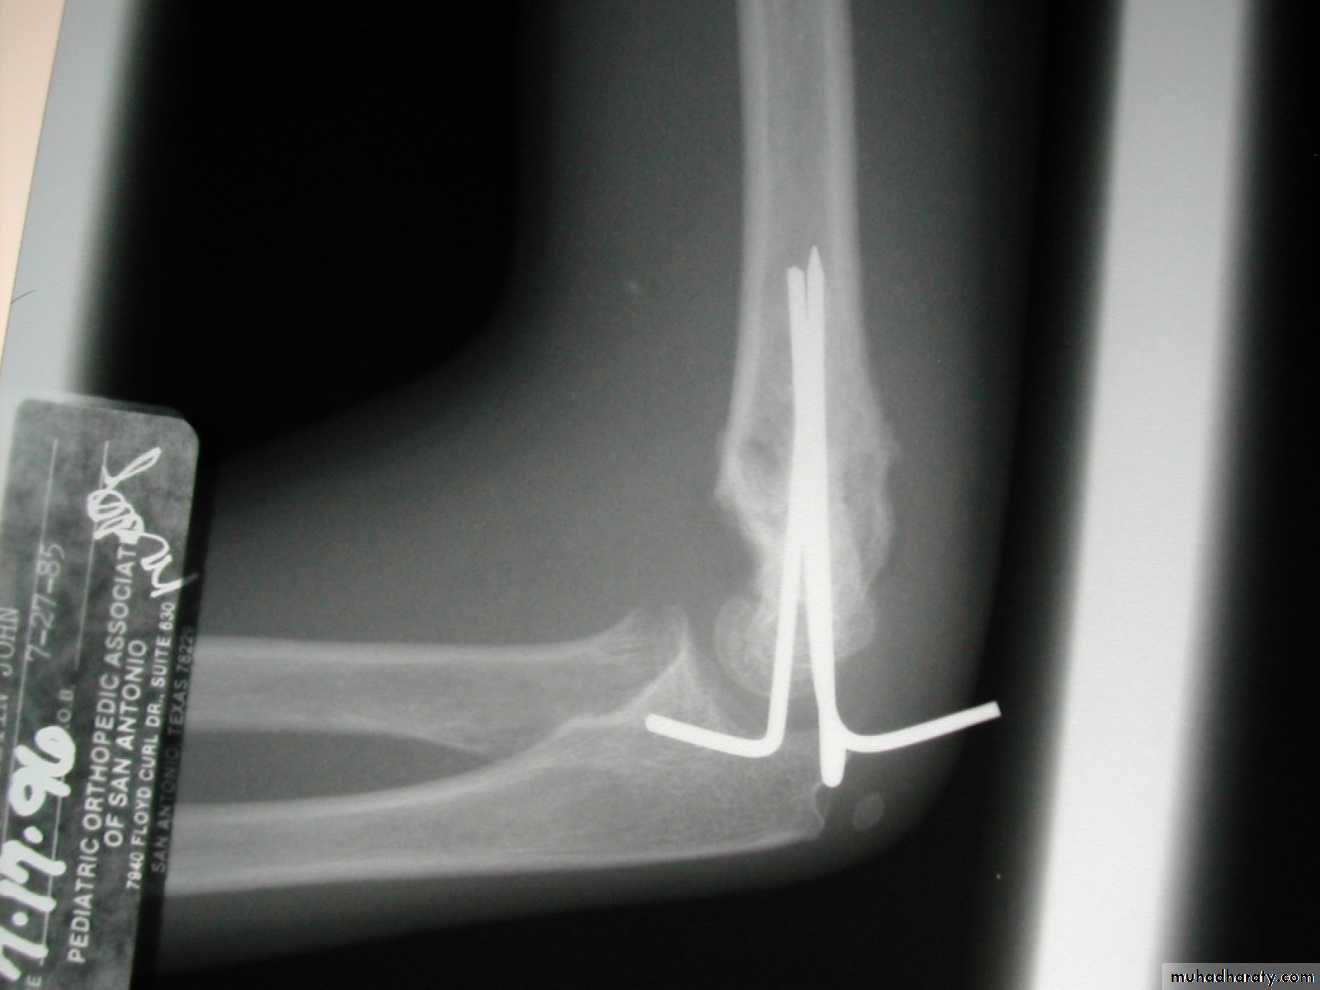

Percutaneous

pin

fixation

If a cast is inadequate,

then what is the standard for maintaining the reduction?

How can the danger of ulnar nerve

injury be minimized?By

making an incision

directly over the

medial epicondyle,

to locate the

medial epicondyleby direct vision.

Then, insert the medial pin by direct vision

into the center of the medial epicondyle.while the ulnar nerve

is

retracted posteriorly.

The pin is inserted,